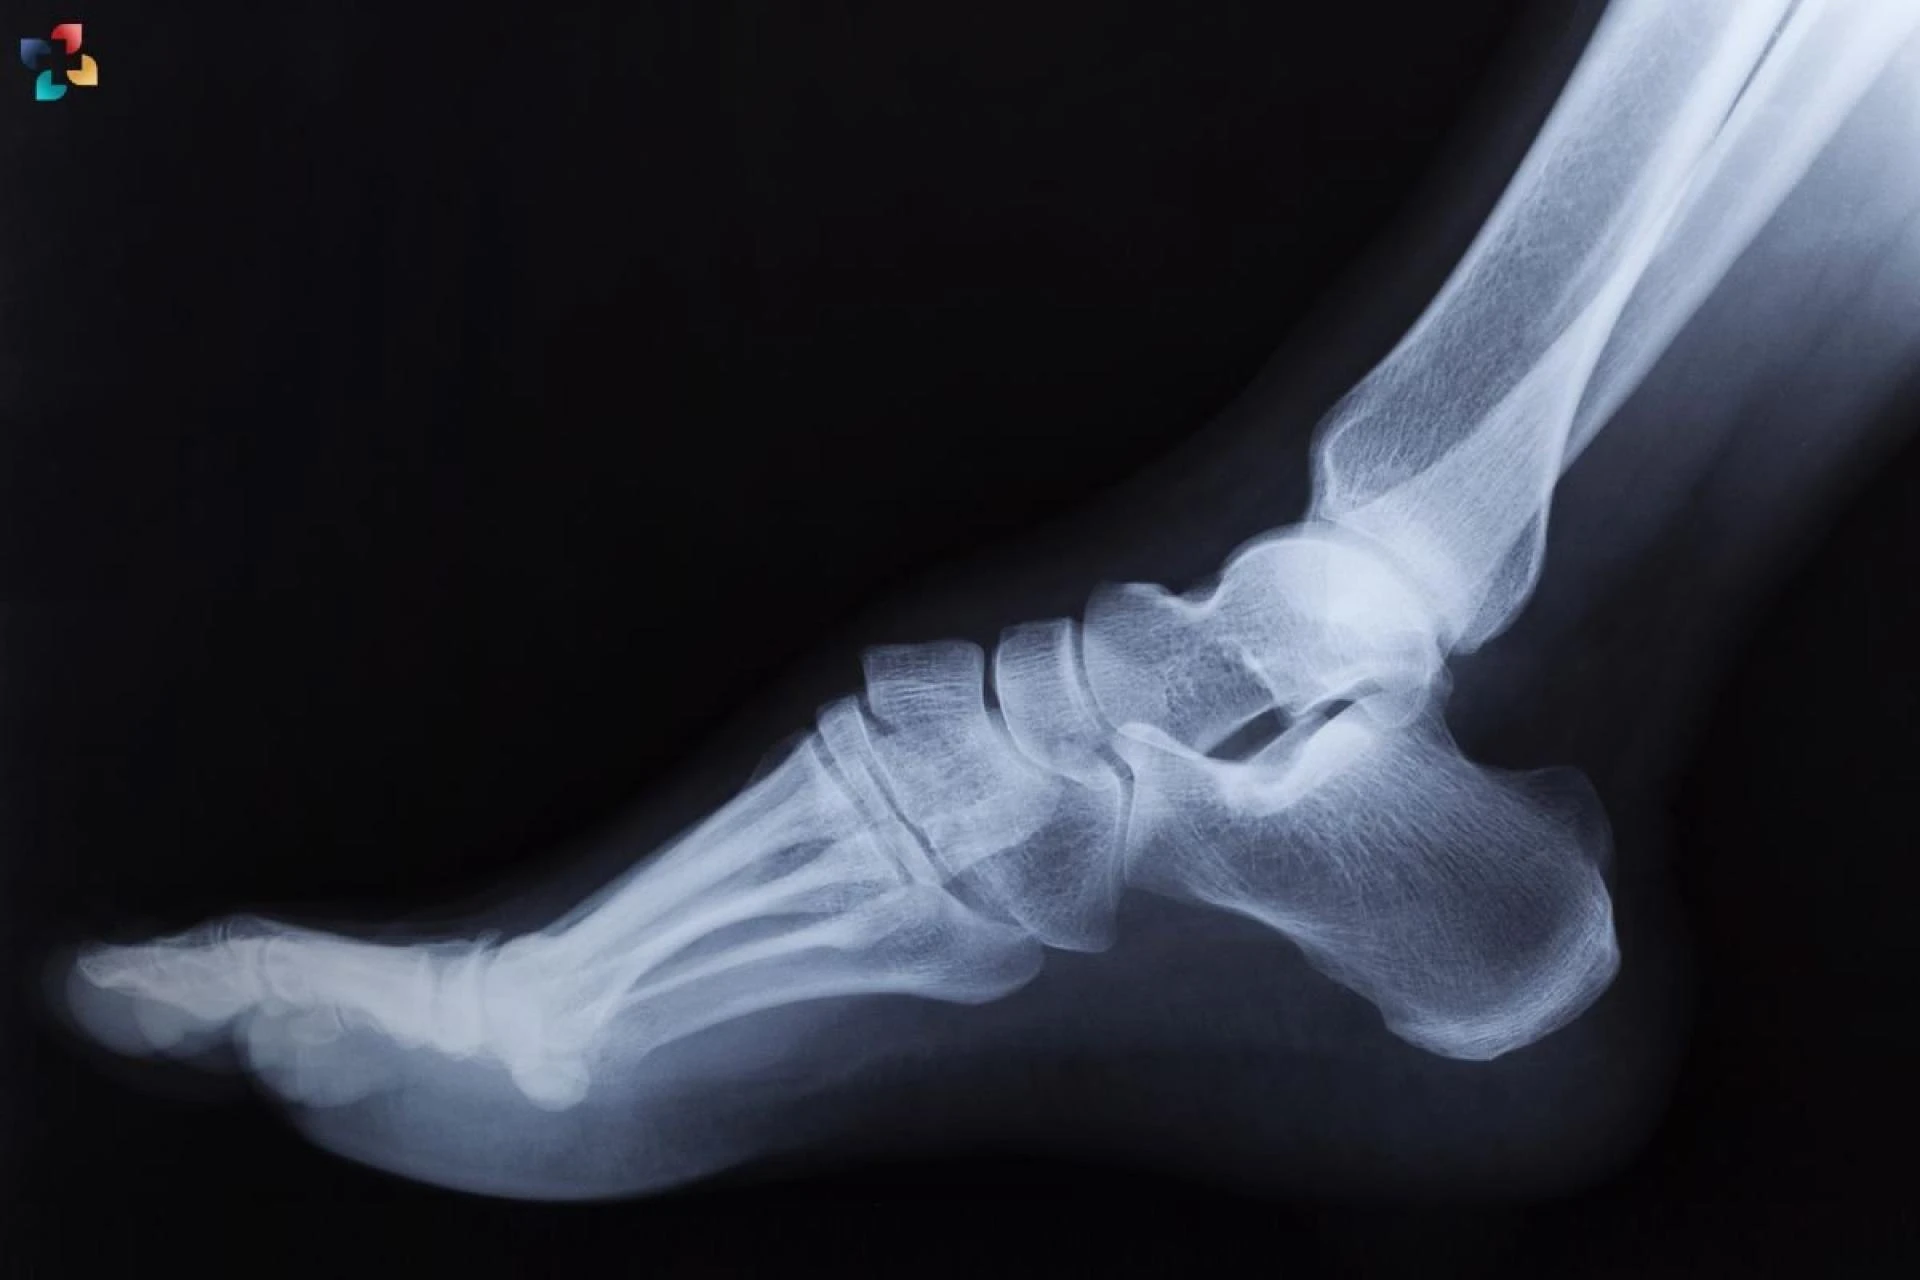

3. Imaging Studies

Imaging studies are essential for confirming the diagnosis of a calcaneal stress fracture. The most common imaging techniques include:

a. X-rays

X-rays can reveal fractures, but early-stage stress fractures may not be visible. In such cases, additional imaging is necessary.